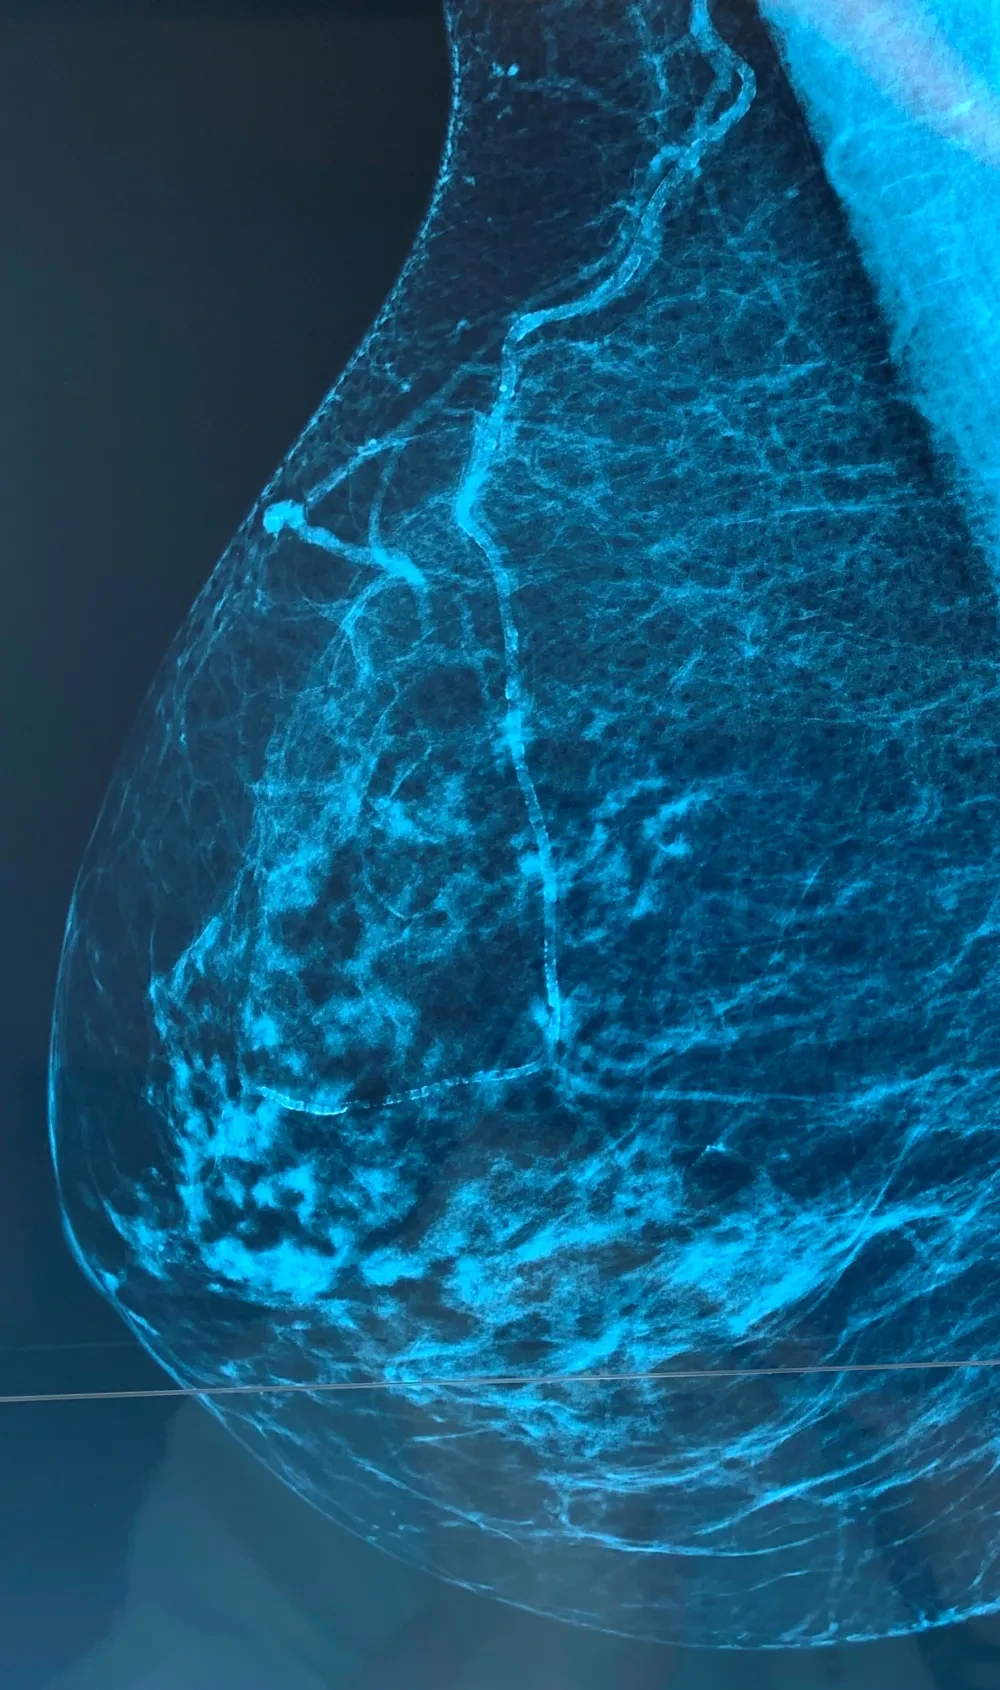

Importance de l'Évaluation par Échographie

L'échographie est un outil de diagnostic essentiel pour évaluer le risque cardiovasculaire.

- * La mesure de l'épaisseur des plaques dans les vaisseaux superficiels est hautement reproductible.

- * La plaque carotidienne est un indicateur de risque accru d'ASCVD, même si elle est inférieure à 3 mm.

- * L'échographie est rapide, peu coûteuse et sans radiation ionisante, ce qui en fait un outil idéal pour la prédiction des risques.

Lz rôle prédictif des calcifications carotidiennes est reconnu vs CAC . Mais dans la pratique ces plaques carotidiennes ne suffisent pas à mon sens et j'ajoute les plaques du segment iliofémoral droit et gauche et les plaques au niveau de l'aorte sous-rénale. Enfin les calcifications mammaires sont aussi très utiles. Cette comptabilisation est simple, les plaques à retenir doivent être au minimum de 2 mm d'épaisseur . Dans la VRAIE VIE les patients concernés sont tous à haut risque CV. Il faut privilégier le NON INVASIF en prévention primaire ! Enfin ne pas oublier que tout cela doit être précédé de la correction "drastique" des FDRCV, sinon à quoi bon vouloir faire une prévention primaire. Evaluer le risque CV en prévention primaire, c'est aussi mesurer l'onde de pouls , l'épaisseur intima média et l'IPS de cheville. C'est ainsi que l'on peut détecter un risque CV significatif chez un patient jeune asymptomatique et alors prescrire une statine en fixant la cible LDL en tenant compte de tous ces paramètres. C'est cost-effective, c'est efficace, ça prend peu de temps et ainsi le cadrage vasculaire du patient est complet. La consultation cardiologique sera systématique.